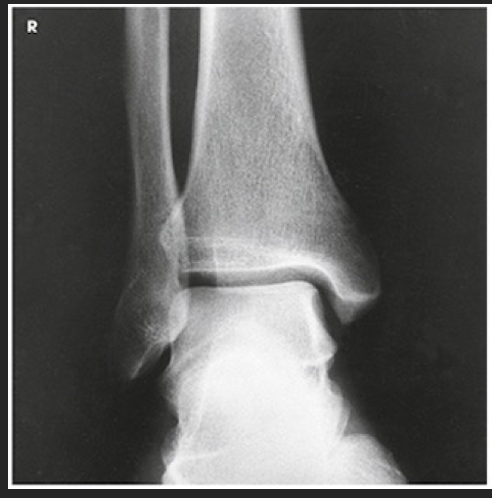

Name this projection.

Lateral ankle

What type of projection is it?

Mediolateral

Which side is the patient turned toward?

Affected side

Where does the CR enter?

Perpendicular to the ankle joint, entering at the medial malleolus

How do you evaluate for a true lateral?

The tibiotalar joint will be well visualized, and the fibula will be over the posterior half of the tibia

How much of the distal tibia and fibula must be included?

1/3

Which joint is well visualized?

Tibiotalar